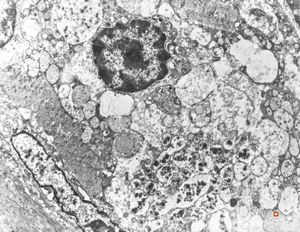

normal seromucinous salivary gland